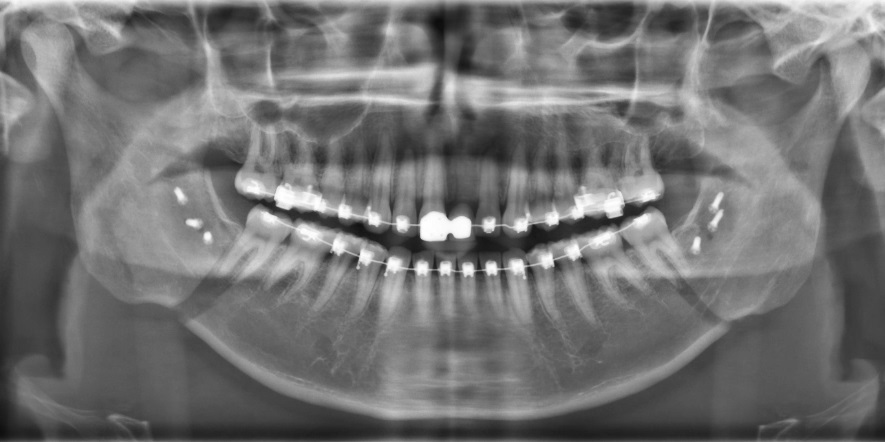

Röntgen beeld na operatie

Orthodontie door Ortho Onderweg, Alphen aan de Rijn

Operatie door W. van Hout, LUMC